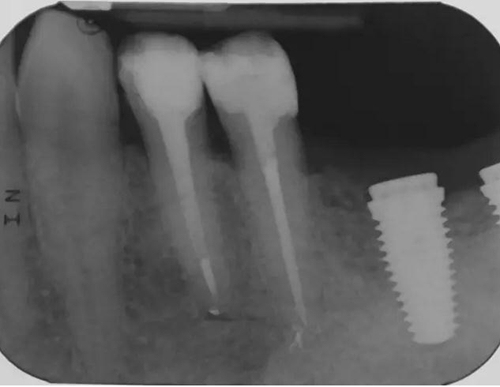

圖4 該病例中,左下4根充失敗,左下5牙髓壞死。兩個牙齒均需要根管治療和修復。

圖5 根管治療術后。左下4需要使用纖維樁,并用雙固化樹脂粘結劑粘結。左下5無需纖維樁。但2個牙齒均需要進行覆蓋牙尖的修復。

圖7 術后片。左下4重新疏通。根尖4mm牙膠封閉,根管內粘結了纖維樁。左下5根尖有根分叉。在根管冠段,可以樹脂(SDR)進入,輔助固位。